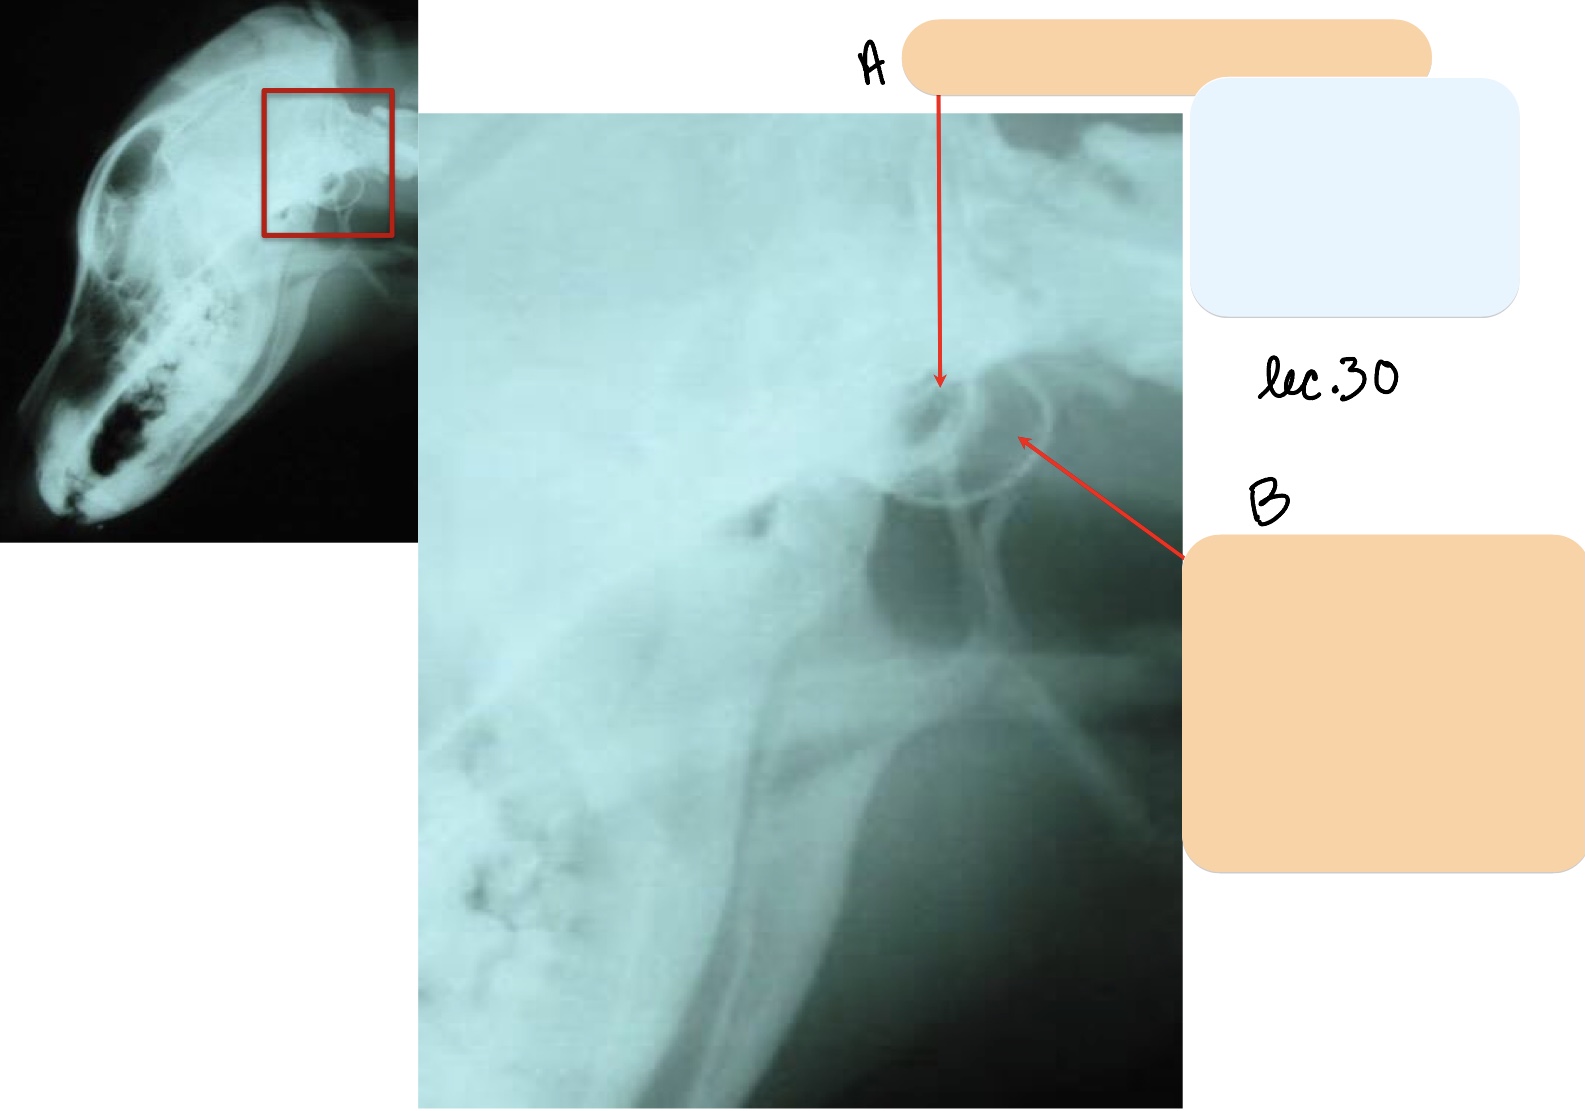

Name the structure(s) indicated by a and b.

zygomatic process

zygomatic arch

Name the structure(s) indicated by a.

mandibular fossa